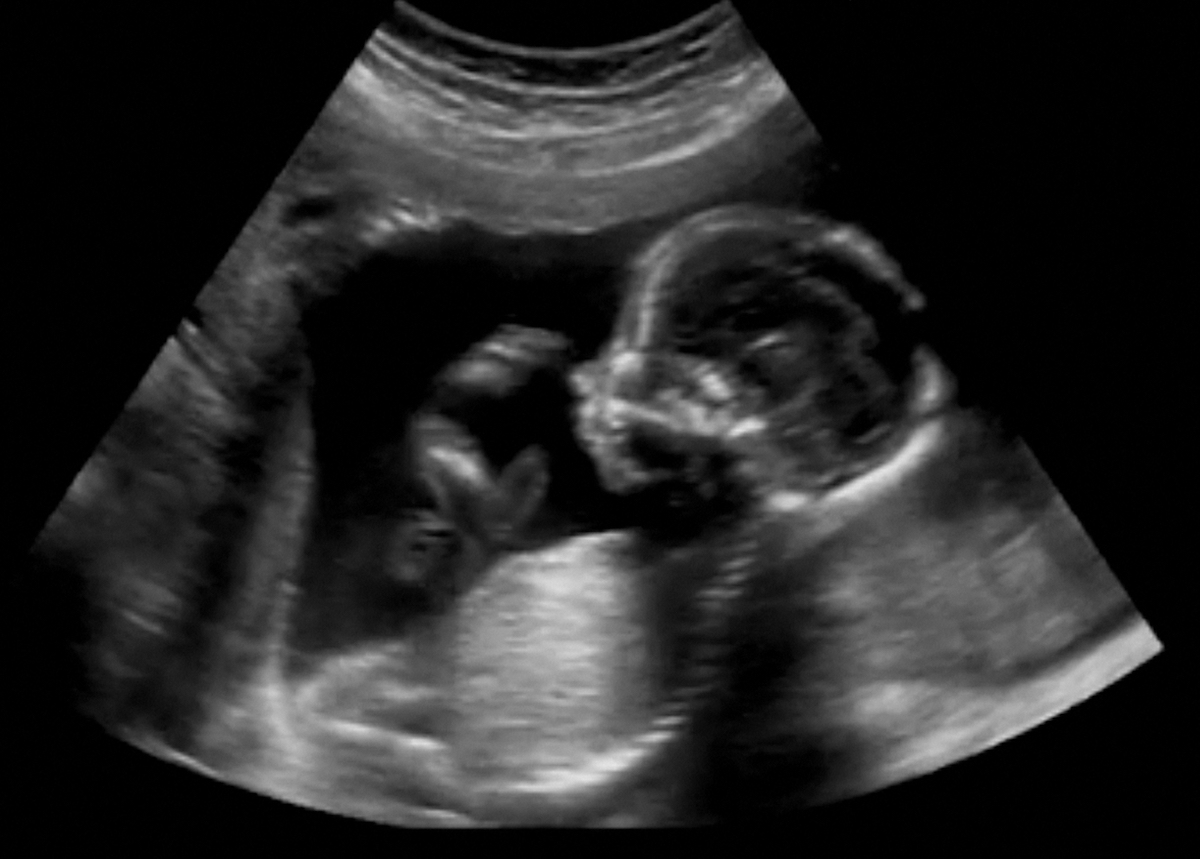

Según publica la OMS en un informe sobre la Evaluación Global del estado de la ciencia sobre los disruptores endocrinos, los disruptores endocrinos pueden producir pubertad precoz, influir en el desarrollo neurológico del feto y en la función neuroendocrina y el comportamiento, alterar el sistema inmunológico, así como incrementar la incidencia de determinados tipos de cáncer, como el de mama, el testicular o el de próstata. Y afectan en mayor medida a los bebés durante el embarazo y a la población infantil, hasta el punto de que algunos estudios muestran que la exposición de los fetos a este tipo de sustancias puede ocasionar problemas como el asma o la obesidad durante la infancia.

Además de lo anterior, es muy importante tener en cuenta que los disruptores endocrinos parecen jugar un papel fundamental en el caso de la fertilidad humana y especialmente en la salud reproductiva del varón, antes incluso de que nazca.

Efectivamente, algunas de estas substancias pueden actuar como estrógenos, de manera que si una mujer está embarazada de un feto masculino, la exposición a estos compuestos puede afectar al correcto desarrollo de los testículos, lo cual afectará no solo a la futura fertilidad de ese hombre (nacerá ya con una capacidad reproductiva reducida), sino que también puede aumentar el riesgo de tener un cáncer de testículo. Por eso se está viendo que en las zonas más industrializadas del planeta, como Europa, Estados Unidos, Australia o Japón, está aumentando no solo la frecuencia de la infertilidad masculina sino también del cáncer de testículo.